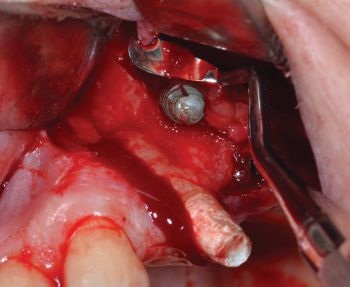

Using microsurgical grasping forceps, the implant was securely clamped and then removed manually (Figs. 11–13).

When Implants Go Rogue

Fig. 11: Localization of the displaced implant

Fig. 12: Implant removal